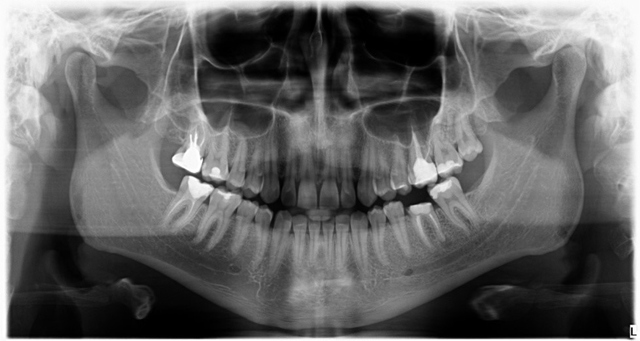

Ryc. 1. Stan kliniczny zęba 36.

Wykonano pantomogram oraz zdjęcie celowane, które ujawniło zmianę okołowierzchołkową przy korzeniu dystalnym. Nie stwierdzono patologii tkanek twardych zębów sąsiadujących z zębem zakwalifikowanym do ekstrakcji, dlatego powzięto decyzję o odbudowie implantologicznej przyszłego braku zębowego (ryc. 1-3).